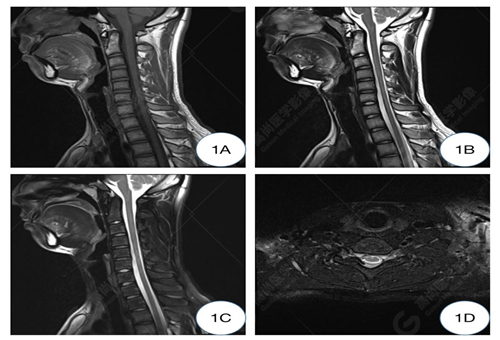

1A-1C圖、常規(guī)仰臥位T1WI及T2WI矢狀位圖示頸椎生理曲度變直,椎體形態(tài)及信號均正常,椎間隙正常,椎管未見狹窄;1D圖、常規(guī)仰臥位T2WI橫軸位示C5-6水平硬膜外間隙未見增寬,相應(yīng)水平頸髓未見受壓。

影像學(xué)常規(guī)中立位可表現(xiàn)為下頸椎和頸背交界處的脊髓萎縮變平,神經(jīng)膠質(zhì)增生區(qū)域在T2WI序列顯示為高信號,有時僅表現(xiàn)出可疑征象,需補充屈曲位掃描。HD 在屈曲 MRI 上具有特征性的成像特征。屈曲位MRI顯示,低位的頸髓向前移位,受壓變扁平,可合并萎縮,后部的硬腦膜向前移位,后硬膜外間隙增寬,形成新月形區(qū)域,并有異常信號改變及流空血管影,增強掃描硬膜外異常信號常呈明顯強化,提示其為充血的后靜脈叢可能,因為其在中立位掃描時完全消失。